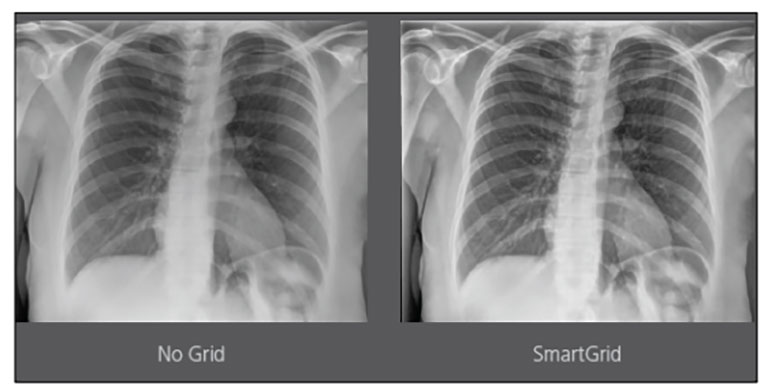

Carestream Introduces New Software Update to Boost Diagnostic Accuracy

Carestream today announced the latest update to its Image Suite V4 Software, MR 11: a series of enhancements to help improve customer confidence and increase diagnostic accuracy [...]

CARESTREAM Image Suite V4 MR11 has set a new standard for workflow efficiency, offering a robust set of features and functionalities to enhance clinical confidence in healthcare professionals. Using an auto-generated companion image from a single exposure, leverage a range of image processing options to increase diagnostic accuracy and enhance patient care.

Our Carestream Focus HD 35/43 Retrofit Detectors, powered by Image Suite Software, are an ideal solution to step up to full digital X-ray for customers who simply cannot compromise on image quality. It seamlessly integrates into existing setups, bringing the power of full digital X-ray with minimal disruption and maximum clarity, along with the following benefits: